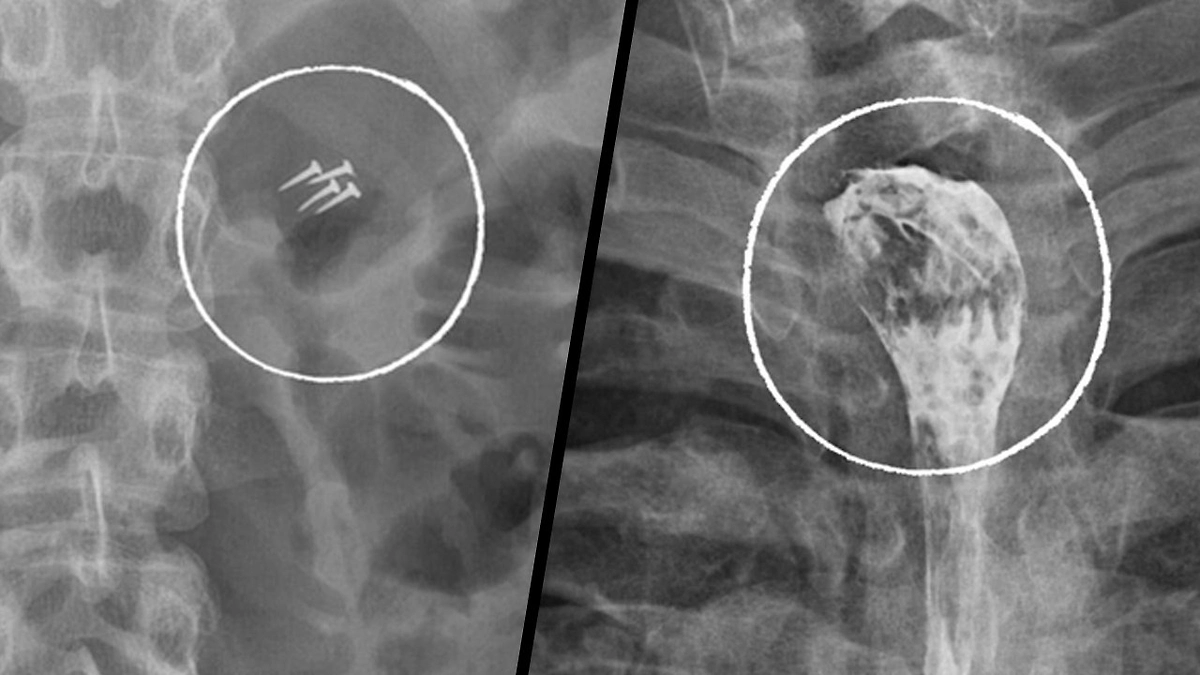

За год медикам пришлось удалять беспроводные наушники, зубные коронки, абрикосовую косточку, черенок ложки, украшения и даже гвозди, которые пациенты случайно проглотили, в том числе во время ремонтных работ.

В клинике отметили, что такие случаи выглядят курьёзно, однако остаются серьёзной проблемой. Ежегодно в Склиф поступают десятки пациентов с инородными телами в организме, которым требуется экстренная помощь, а в некоторых случаях — длительное восстановление после хирургического вмешательства.